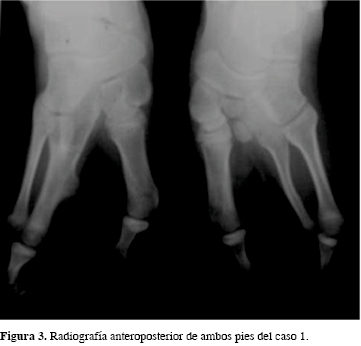

En la radiografía simple de pies se observa la presencia de tres metatarsianos con fusión del tercero y cuarto del lado derecho. Desarrollo bilateral de falanges en el primer dedo y de los dedos quinto izquierdo y cuarto derecho (Figura 3).

No se detectaron otras alteraciones dismórficas y la valoración antropométrica fue normal. Tampoco se encontraron otras alteraciones físicas o sistémicas al momento del examen. Se clasificó como una ectrodactilia tipo 1 de Abraham y grado IV de Blauth y Borisch.